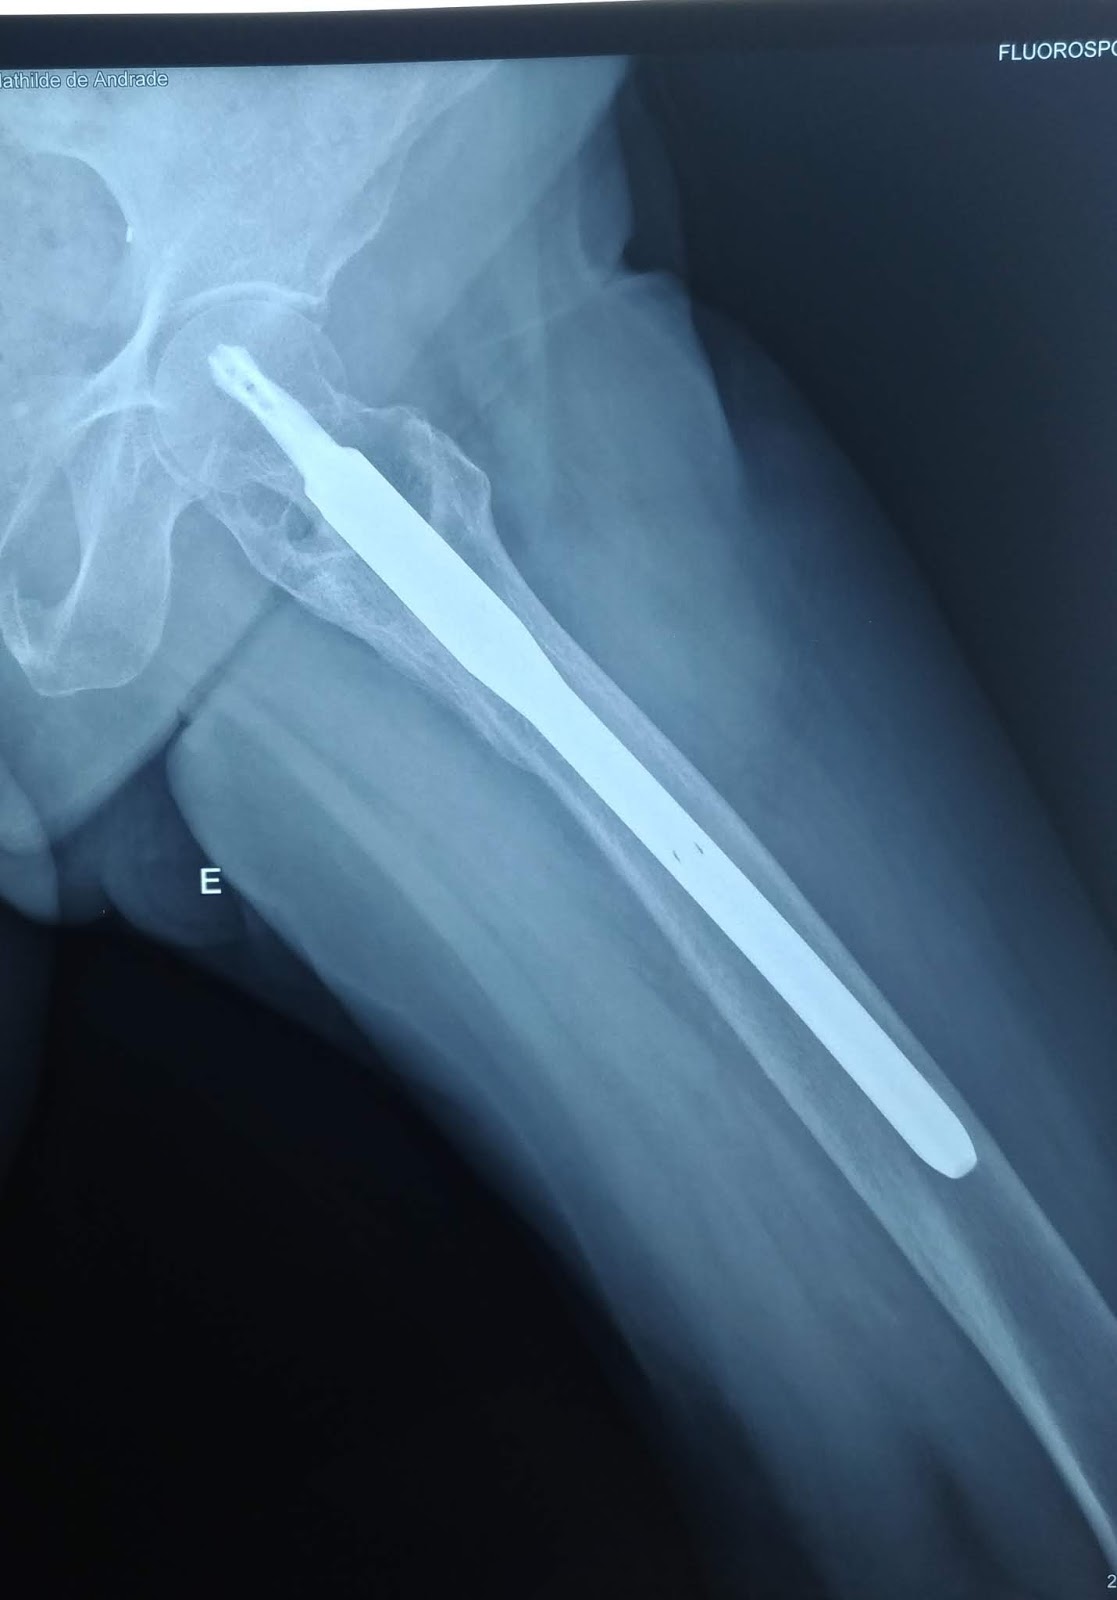

Fratura Transtrocantérica do Femur Dr. Luiz Marchese YouTube

Fractura pertrocantérica do fémur esq e seu tratamento cirurgico Enfermagem em Ortopedia

Fraturas do Quadril Transtrocanteriana e Colo do Fêmur